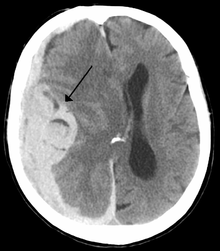

Midline shift

Midline shift is a shift of the brain past its center line.[1] The sign may be evident on neuroimaging such as CT scanning.[1] The sign is considered ominous because it is commonly associated with a distortion of the brain stem that can cause serious dysfunction evidenced by abnormal posturing and failure of the pupils to constrict in response to light.[1] Midline shift is often associated with high intracranial pressure (ICP), which can be deadly.[1] In fact, midline shift is a measure of ICP; presence of the former is an indication of the latter.[2] Presence of midline shift is an indication for neurosurgeons to take measures to monitor and control ICP.[1] Immediate surgery may be indicated when there is a midline shift of over 5 mm.[3][4] The sign can be caused by conditions including traumatic brain injury,[1]stroke, hematoma, or birth deformity that leads to a raised intracranial pressure.

Three main structures are commonly investigated when measuring midline shift. The most important of these is the septum pellucidum, which is a thin and linear layer of tissue located between the right and left ventricles.[7] It is easily found on CT or MRI images due to its unique hypodensity.[7] The other two important structures of the midline include the third ventricle and the pineal gland which are both centrally located and caudal to the septum pellucidum.[6][7] Identifying the location of these structures on a damaged brains compared to an unaffected brain is another way of categorizing the severity of the midline shift. The terms mild, moderate, and severe are associated with the extent of increasing damage.